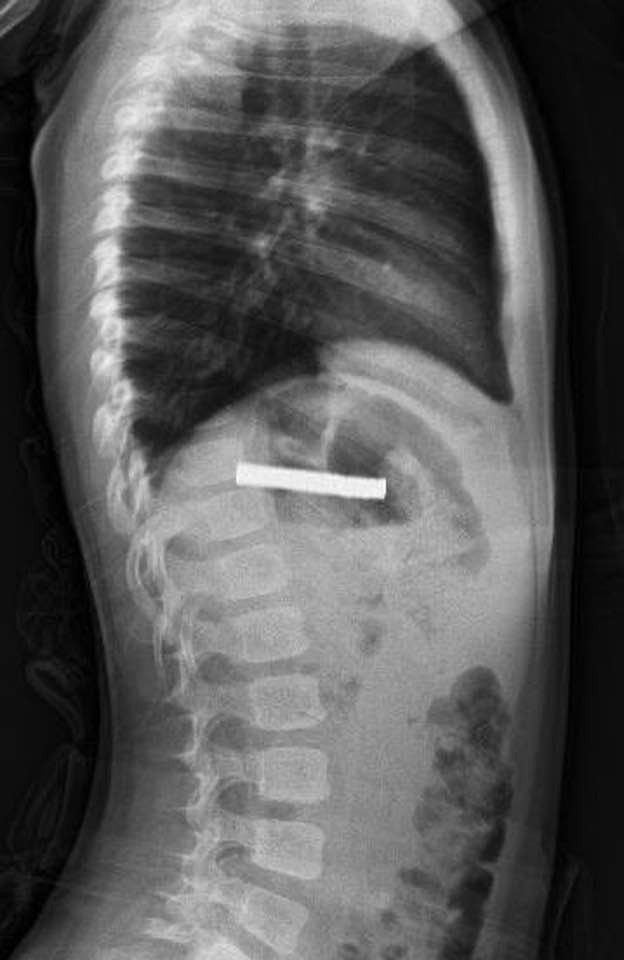

Fırat Üniversitesi Çocuk Gastroenteroloji Hepatoloji ve Beslenme Bilim Dalı Başkanı Prof. Dr. Yaşar Doğan ve ekibi tarafından gerçekleştirilen endoskopik operasyonla çocuğun yemek borusuna yapışan 19 mıknatıs başarıyla çıkarıldı.

Mıknatısların uzun süre yemek borusunda kalması nedeniyle yemek borusu ve mide girişinde zedelenmeler meydana geldiği, ancak çocuğun genel sağlık durumunun iyi olduğu ve kısa süre sonra taburcu edildiği öğrenildi.